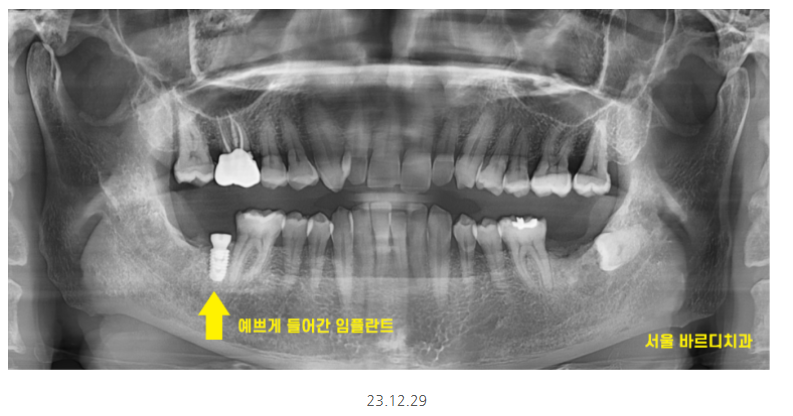

하남시청치과 임플란트 그 결과는,,?

짜잔~~

원하는 위치에 정확히 들어갔습니다.

3개월 뒤에 뼈와 충분히 붙어서

기둥을 올리고 보철을 올려드렸습니다.